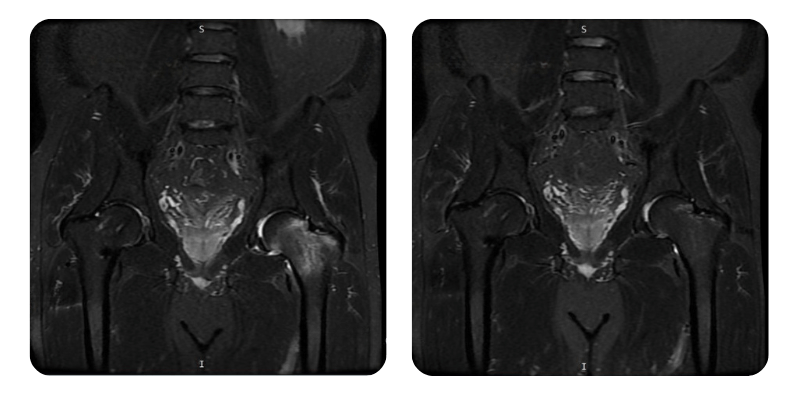

Vorher

Nachher

B.A.M., 56 Jahre – Avasculäre Nekrose von linkem Femurkopf und -hals nach Fraktur des rechten Femurhalses

Diagnose: Avasculäre Nekrose von Femurkopf und -hals links nach Fraktur des rechten Femurhalses.

Therapeutische Maßnahmen: 20 Sitzungen hyperbarer Sauerstofftherapie.

Verlauf: Nach Abschluss der 20 Sitzungen hyperbarer Therapie zeigt der Patient eine Besserung von etwa 90 %, mit vollständigem Verschwinden der Lenden- und Hüftbeschwerden. Die Mobilität hat sich deutlich verbessert, ohne nächtliche Schmerzen und ohne Bedarf an zusätzlichen Interventionen.